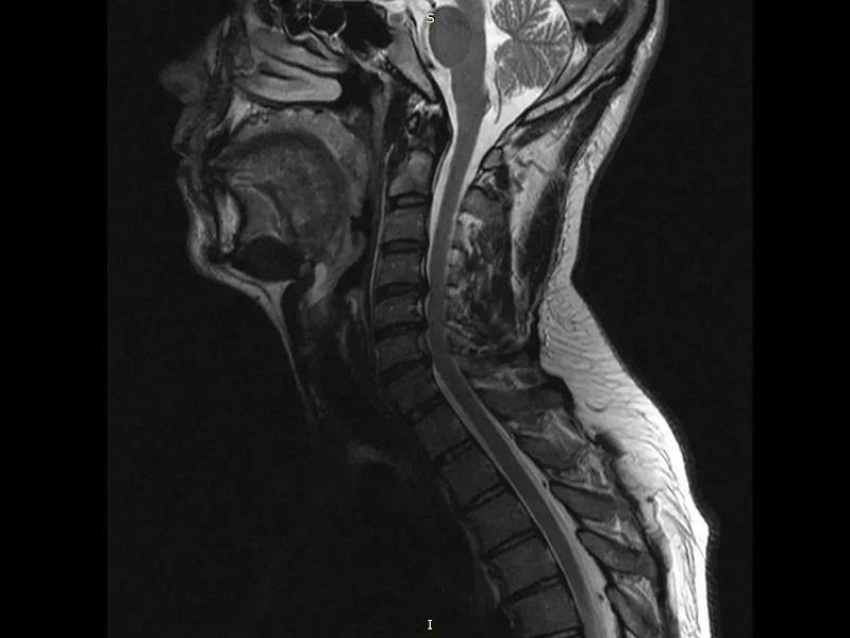

В стационаре БСМП №1 мужчине диагностировали «диско-остеофитный стеноз позвоночного канала на уровне C3-C4, C4-C5, C5-C6, C6-C7». У него на уровне ряда шейных позвонков произошло сужение, а находящиеся в нём структуры сдавливались.

«Уникальность операции заключалась в комбинированной технике. Медики во главе с заведующим нейрохирургическим отделением Павлом Юровым устранила сжатие и стабилизировала позвоночник, одновременно с этим укрепив его разными титановыми конструкциями», – отметили в Минздраве.